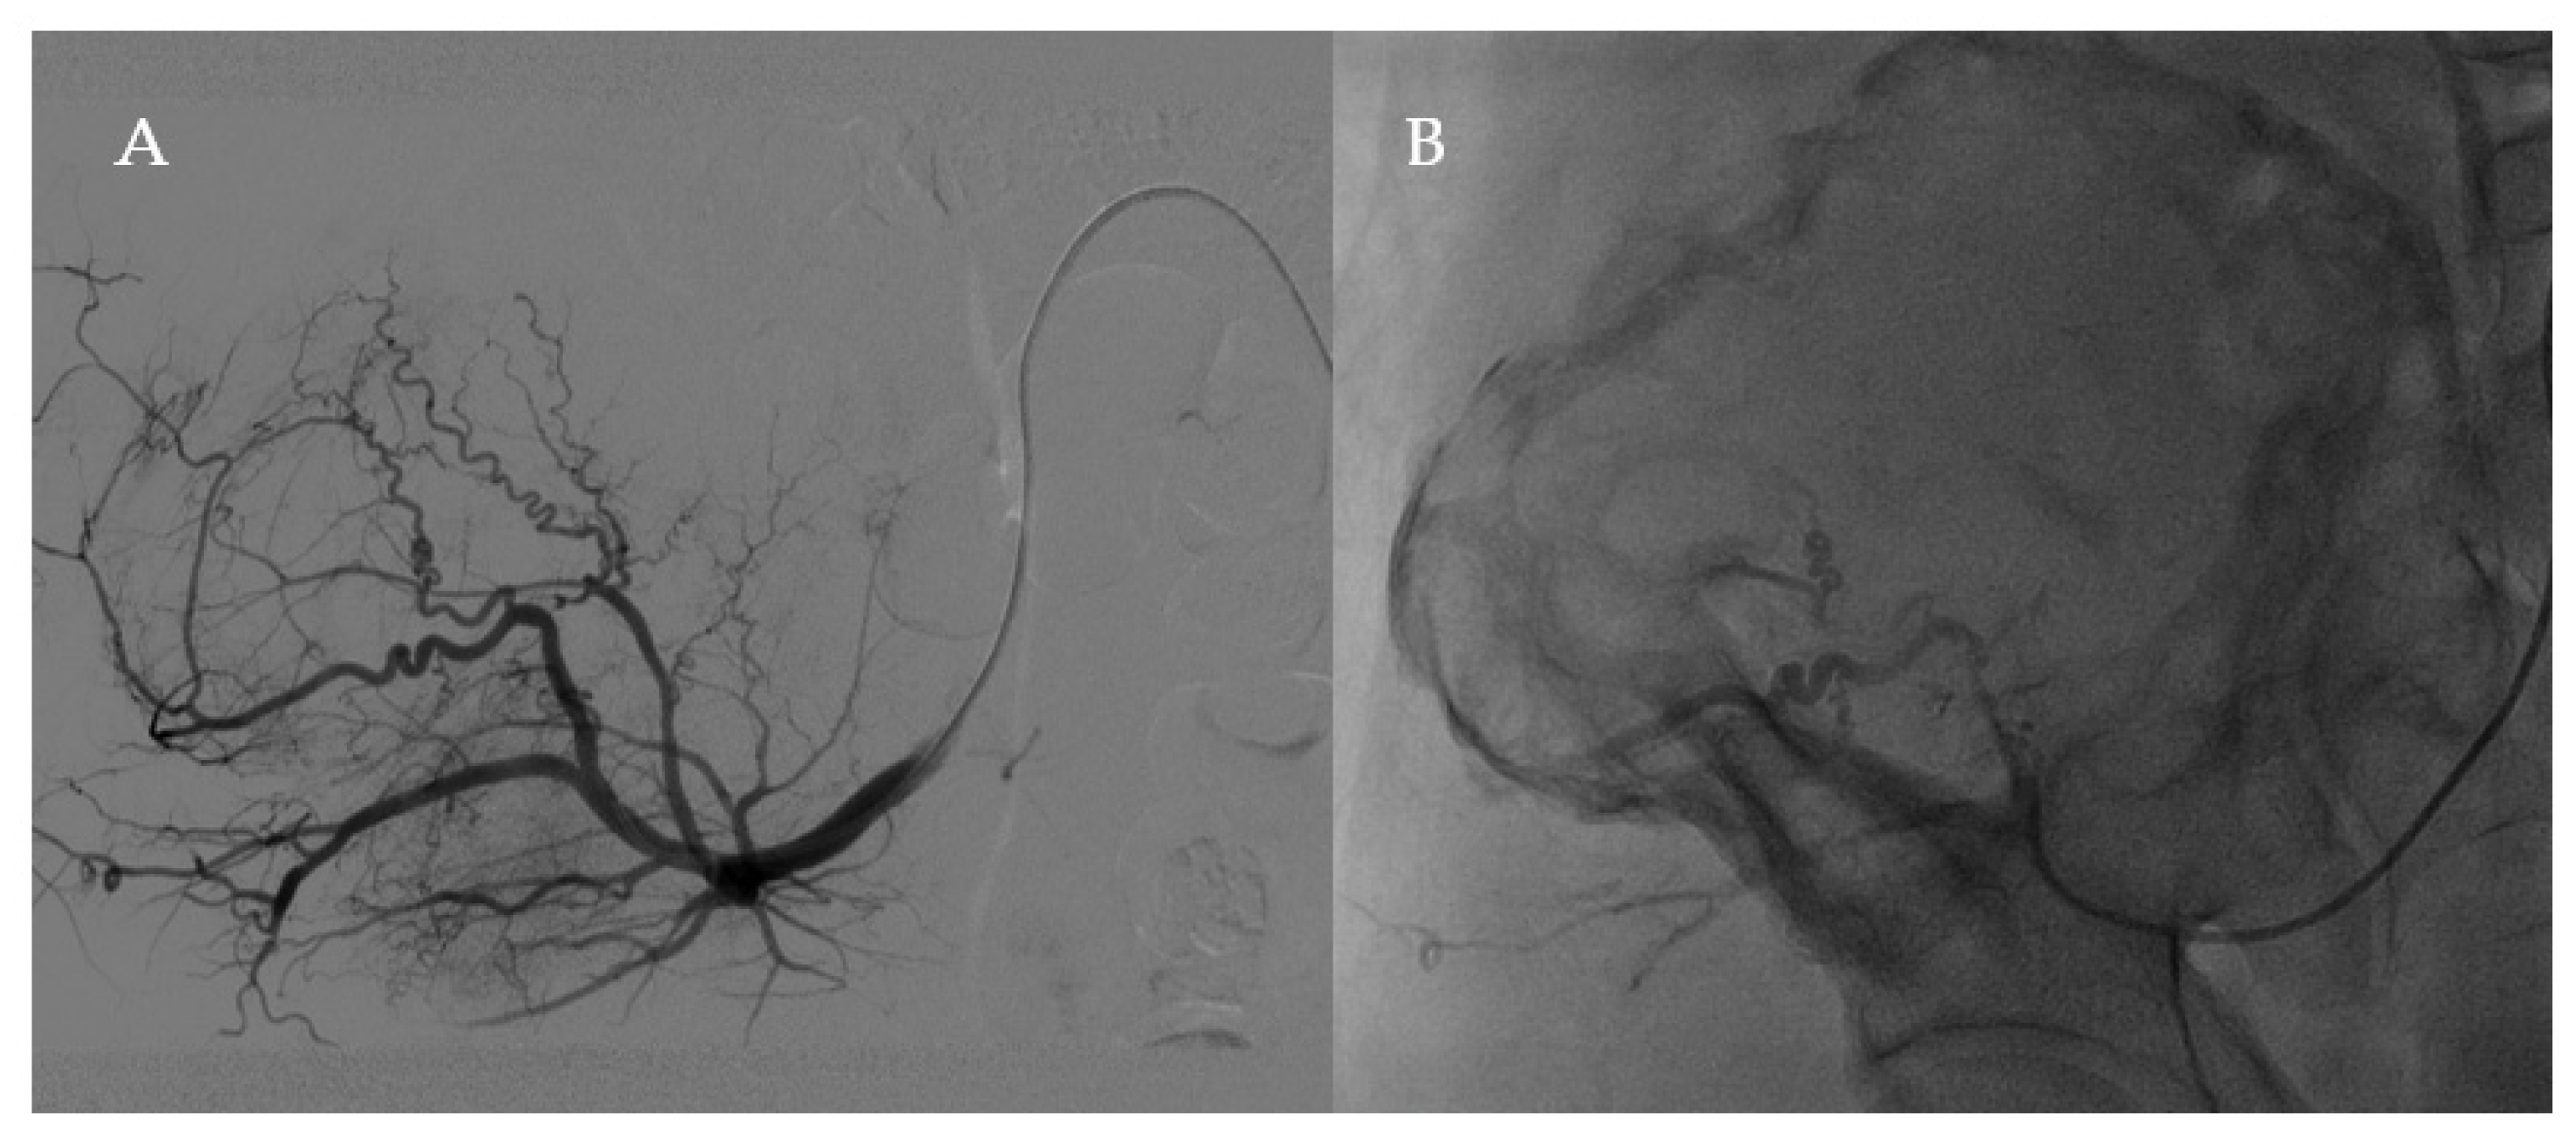

2.2. Surgery